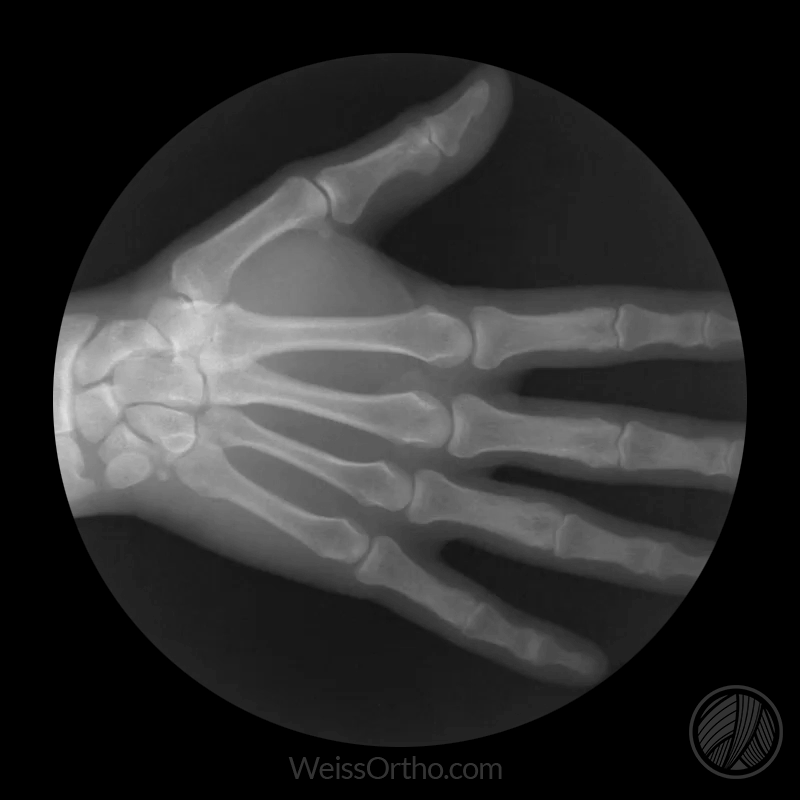

Show your bones.

These X-ray gifs show just what happens to joints in motion. The gifs were made by Cameron Drake for orthopaedic surgeon Dr Noah Weiss. You can see more videos of joints in motion on Dr Weiss's YouTube page.